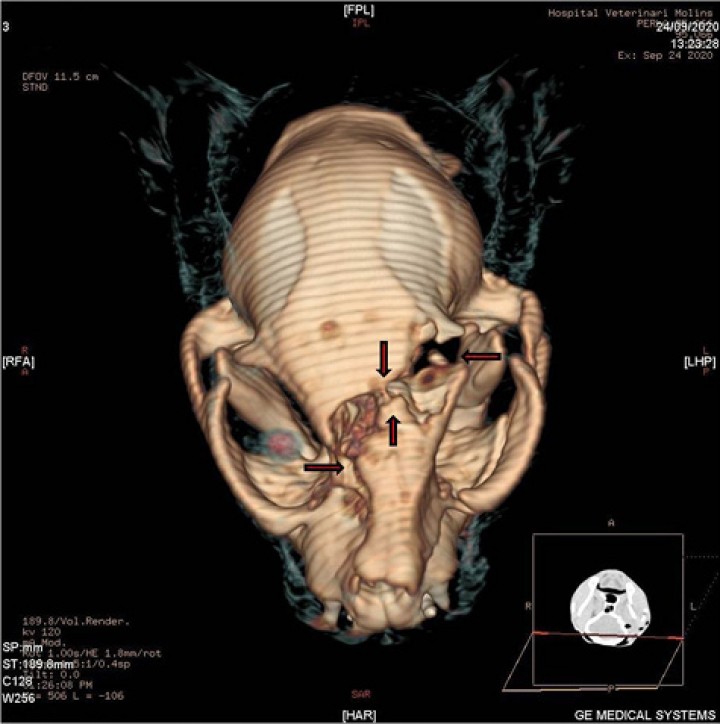

<p>TAC de revisión. Cortes transversales en algoritmo de hueso del TAC de revisión, adquirido en algoritmo de tejido blando y hueso con un grosor de 2 mm. (<strong>A</strong>) Se observa una fractura simple y deprimida en la parte temporal del hueso frontal izquierdo (flecha blanca), desplazamiento de la fosa etmoidal en su unión con el hueso frontal del lado derecho (flecha amarilla), desplazamiento del meato etmoidal y preesfenoides (flecha negra), y fractura simple de la lámina perpendicular derecha del hueso palatino (flecha azul). Además, se aprecia una lesión redonda de bordes bien definidos, hipoatenuante e intracraneal justo en la fractura de la parte temporal del hueso frontal izquierdo (flecha sólida), así como enfisema subcutáneo sobre dicho hueso (asterisco). (<strong>B</strong>) Corte a la altura de las bullas timpánicas en el que se observan dos lesiones intracraneales (con sospecha de ser intraventriculares), redondas, de bordes bien definidos e hipoatenuantes (flechas), con contenido de densidad aire (entre 976 y 1000,05 HU). Además, se observa enfisema subcutáneo a nivel temporal y parietal en el lado derecho (asteriscos).</p>

TAC de revisión. Cortes transversales en algoritmo de hueso del TAC de revisión, adquirido en algoritmo de tejido blando y hueso con un grosor de 2 mm. (A) Se observa una fractura simple y deprimida en la parte temporal del hueso frontal izquierdo (flecha blanca), desplazamiento de la fosa etmoidal en su unión con el hueso frontal del lado derecho (flecha amarilla), desplazamiento del meato etmoidal y preesfenoides (flecha negra), y fractura simple de la lámina perpendicular derecha del hueso palatino (flecha azul). Además, se aprecia una lesión redonda de bordes bien definidos, hipoatenuante e intracraneal justo en la fractura de la parte temporal del hueso frontal izquierdo (flecha sólida), así como enfisema subcutáneo sobre dicho hueso (asterisco). (B) Corte a la altura de las bullas timpánicas en el que se observan dos lesiones intracraneales (con sospecha de ser intraventriculares), redondas, de bordes bien definidos e hipoatenuantes (flechas), con contenido de densidad aire (entre 976 y 1000,05 HU). Además, se observa enfisema subcutáneo a nivel temporal y parietal en el lado derecho (asteriscos).

¿Qué ha ocurrido entre los dos TACs?

El aire acumulado en las distintas zonas ha entrado a través de una fístula (Fig. 3) y se ha instaurado un gradiente de presión negativo hacia la cavidad craneal situándose probablemente en los ventrículos laterales, provocando un gran aumento del tamaño de los mismos y adoptando una forma redondeada.

Se observaron fracturas en los huesos de las tres principales subdivisiones del cráneo: cara (maxilar, palatino), bóveda craneal (frontal y etmoides) y base de cráneo (preesfenoides). El estudio completo del TAC reveló fracturas conminutas y simples, la mayoría desplazadas y/o deprimidas (Fig. 4).